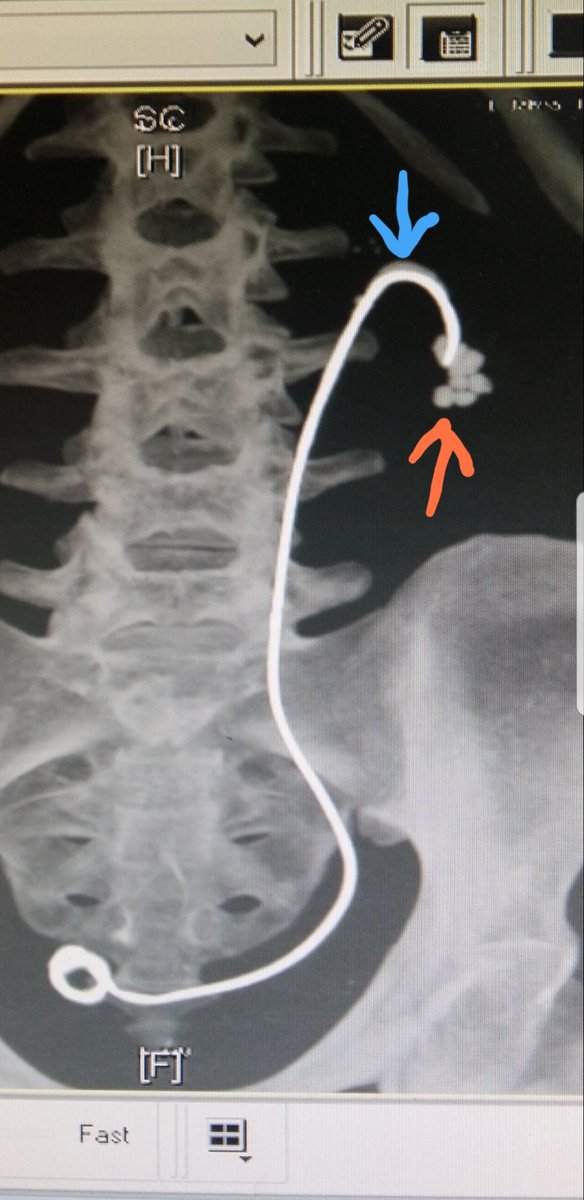

د نايف العنزي On Twitter دعامة حالب نسي المريض المتابعه لإزالتها منذ أكثر من ٧ سنوات التكلسات على جسم الدعامه عند السهم الأزرق تكوين حصوات جديده عند طرف الدعامه عند السهم الأحمر